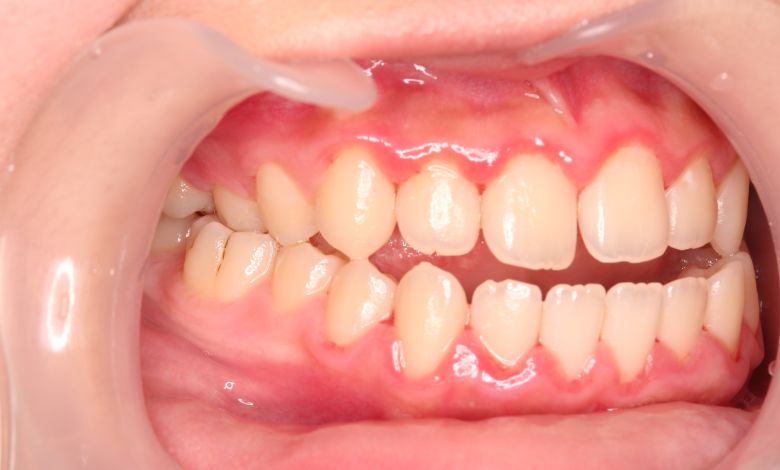

他院にて上下左右4本の抜歯を前提とした矯正治療を提案されていました。上顎・下顎ともに歯列弓が狭く、

V字型の弓状を呈していたため、叢生(歯の重なり)が強く、噛み合わせにも不調和が見られる状態でした。

上顎歯列はV字型に近く、全体的にアーチが狭窄している状態

上下の咬合関係も不正で、機能的にも審美的にも問題のある状態でした